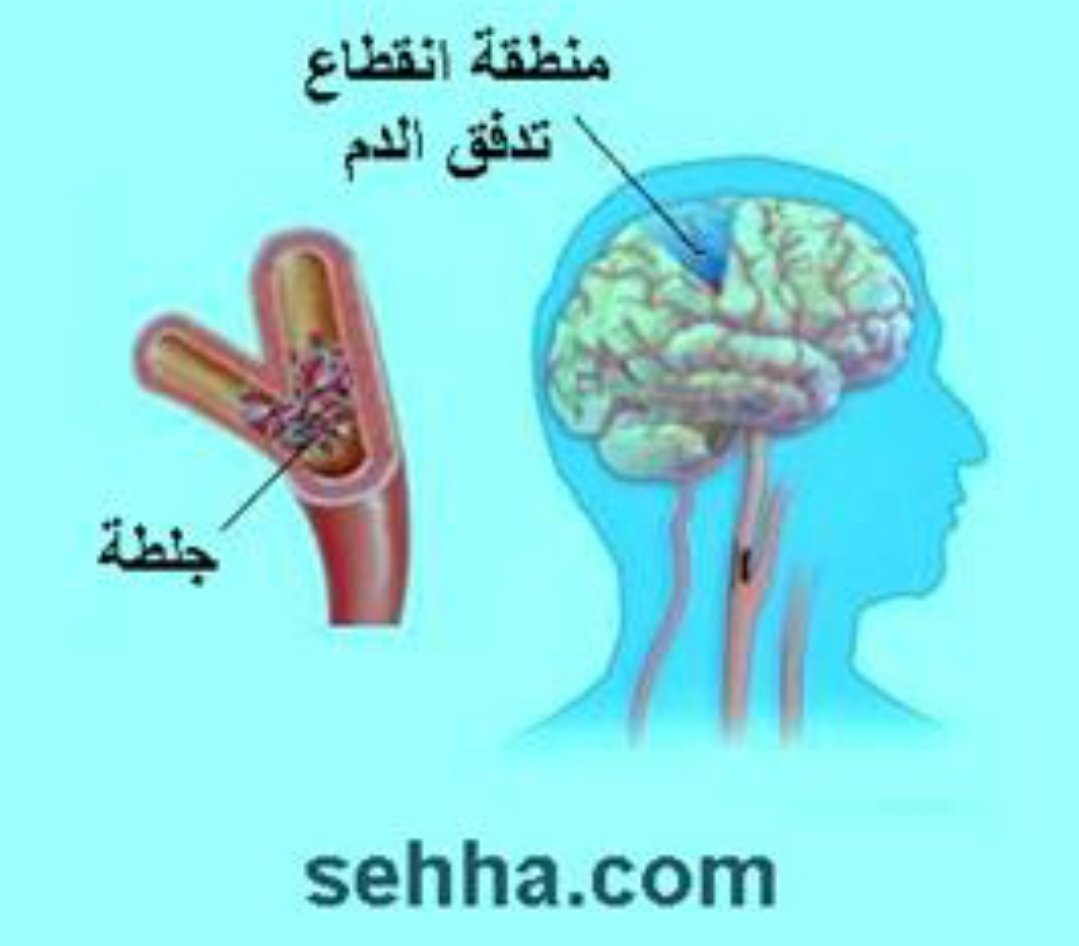

💥هي نقص ترويه الدم (الاوكسجين) لمنطقه بالمخ اوالحبل الشوكي اوشبكية العين

🧠 انسداد في الشرايين (#السكته_الدماغيه_الاقفاريه)

بسبب #خثرة مثلا

#السكته_الدماغيه_الاقفاريه

💥هي نقص في ترويه الدم للمخ اوالحبل الشوكي اوشبكيةالعين

💥بسبب (انسداد أو تضيق) في شرايين(القلب،الرقبه،الراس) الموصله للدم او الاورده المصرفه